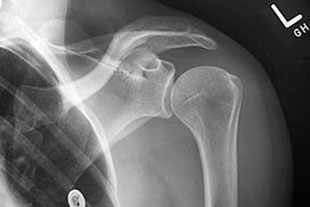

Das Schultergelenk ist ein komplexes Gelenk mit vielen Bewegungsfreiheiten und wird von einem kräftigen Muskel- und Sehnenmantel umgeben und von einem knöchernen Dach bedeckt.

Die häufigste Ursache akuter Schulterschmerzen ist das sogenannte Engpass-Syndrom (Impingementsyndrom) unter dem Schulterdach bedingt durch einen kleinen knöchernen Sporn, der bei Seitwärtsbewegung des Armes eine Schleimbeutelentzündung auslösen kann und Druck auf die Rotatorenmanschette ausübt. Auch ohne Unfall kann es hierbei, gerade bei älteren Patienten, zu Rissen der Rotatorenmanschette (= Muskel-Sehnen-Kappe der Schulter) kommen, die dann auch eine aktive Bewegungseinschränkung bewirken. Unfallbedingt können akute Risse der Rotatorenmanschette auftreten. Bei einer Schulterluxation (Auskugeln des Schultergelenkes) kann es zu Verletzungen im Bereich der Schulterpfanne bzw. der Gelenklippe (Bankart-Läsion) kommen.

Die Erstdiagnostik bei akuten Schulterschmerzen besteht in der Sonographie (Ultraschalluntersuchung) und einer Röntgenuntersuchung. Hierbei kann bereits sehr genau auf die Ursache der Schmerzsymptomatik geschlossen werden. Sowohl die Rotatorenmanschette (= Muskel-Sehnen-Kappe der Schulter) als auch das Schulterdach und eventuell entzündete Schleimbeutelveränderungen können sehr genau lokalisiert und in der Ausdehnung erkannt werden.

Möglicherweise vorhandene Kalkdepots kommen ebenfalls zur Darstellung. Speziell bei Schulterluxationen (Auskugeln des Schultergelenkes) und Schulterschmerzen nach einem Unfall empfiehlt sich die Durchführung einer kernspintomografischen Untersuchung (MRT), weil hierbei die Ausdehnung von Rotatorenmanschettenrissen oder eine eventuelle Gelenklippenverletzung genau dargestellt werden können.